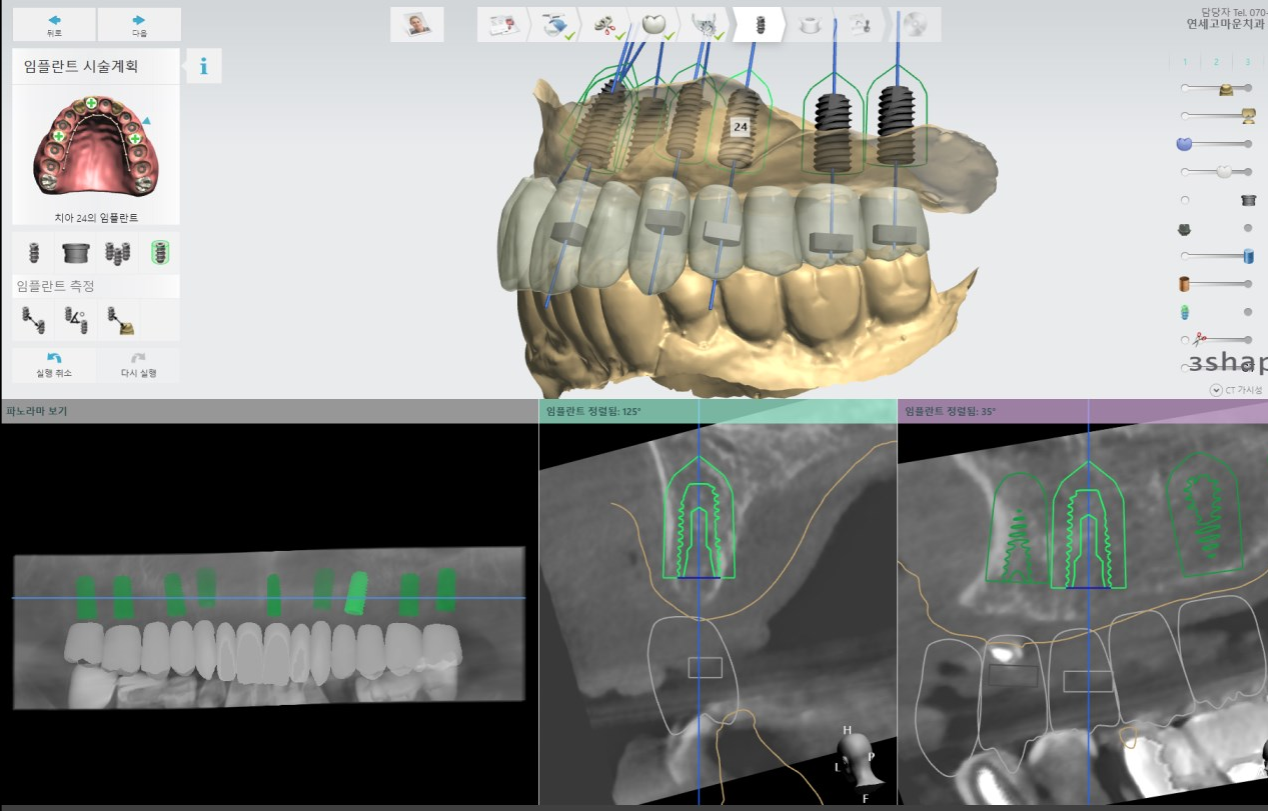

네비게이션 임플란트

네비게이션 임플란트는 절개를 하지 않는 '무절개'시술로 통증, 붓기, 출혈이 거의 없습니다.

미리 만들어진 가이드를 따라 시술하여 수술 시간이 매우 단축됩니다.

첨단 컴퓨터 모의 시술과 수술유도장치로 정밀하고 안전한 수술이 가능하며 신경손상의 가능성과 상악동 감염의 가능성이 매우 낮습니다.

3D 시뮬레이션을 통해 정확한 시술부위에 정밀한 방향으로 식립이 가능하여 최상의 보철물 결과를 얻을 수 있습니다.